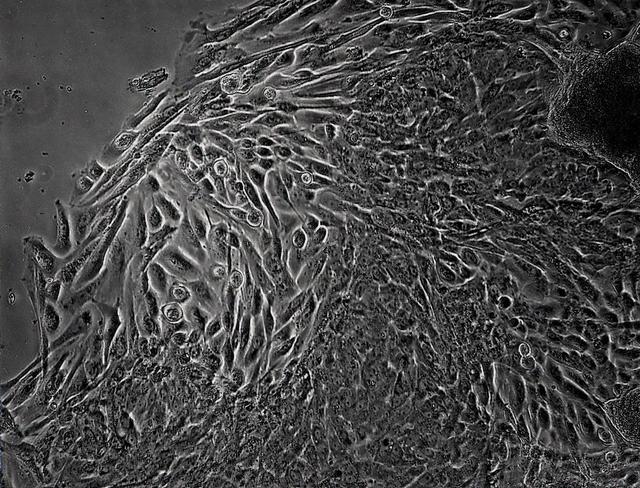

Epithelial cell monoculture: Long-term growth of human mammary epithelial cells (HMEC) grown in monoculture as 3-dimensional constructions in the presence of attachment beads in the NASA Bioreactor. A: A typical construct about 3.5 mm (less than 1/8th inch) in diameter with slightly dehydrted, crinkled beads contained on the surface as well as within the 3-dimensional structure. B: The center of these constructs is hollow. Crinkling of the beads causes a few to fall out, leaving crater-like impressiions in the construct. The central impression shows a small hole that accesses the hollow center of the construct. C: A closeup view of the cells and the hole the central impression. D: Closer views of cells in the construct showing sell-to-cell interactions. NASA's Marshall Space Flight Center (MSFC) is sponsoring research with Bioreactors, rotating wall vessels designed to grow tissue samples in space, to understand how breast cancer works. This ground-based work studies the growth and assembly of human mammary epithelial cell (HMEC) from breast cancer susceptible tissue. Radiation can make the cells cancerous, thus allowing better comparisons of healthy vs. tunorous tissue. Credit: Dr. Robert Richmond, NASA/Marshall Space Flight Center (MSFC).